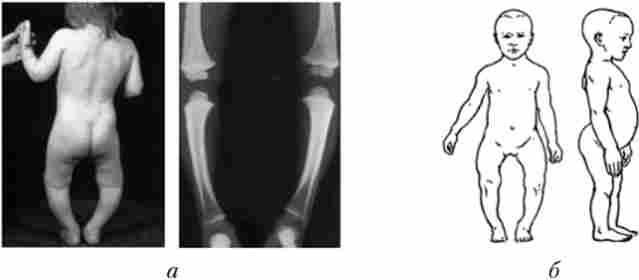

Зміна скелета при рахіті

Мал. 7.23. Зміна скелета при рахіті:

а - викривлення ніг; б - деформація черепа, хребта, грудної клітини

ний формування скелета (рис. 7.23, 7.24), що в свою чергу відбивається на функціях внутрішніх органів. Станом кісткової системи дітей і підлітків можна судити про їх фізичний розвиток.